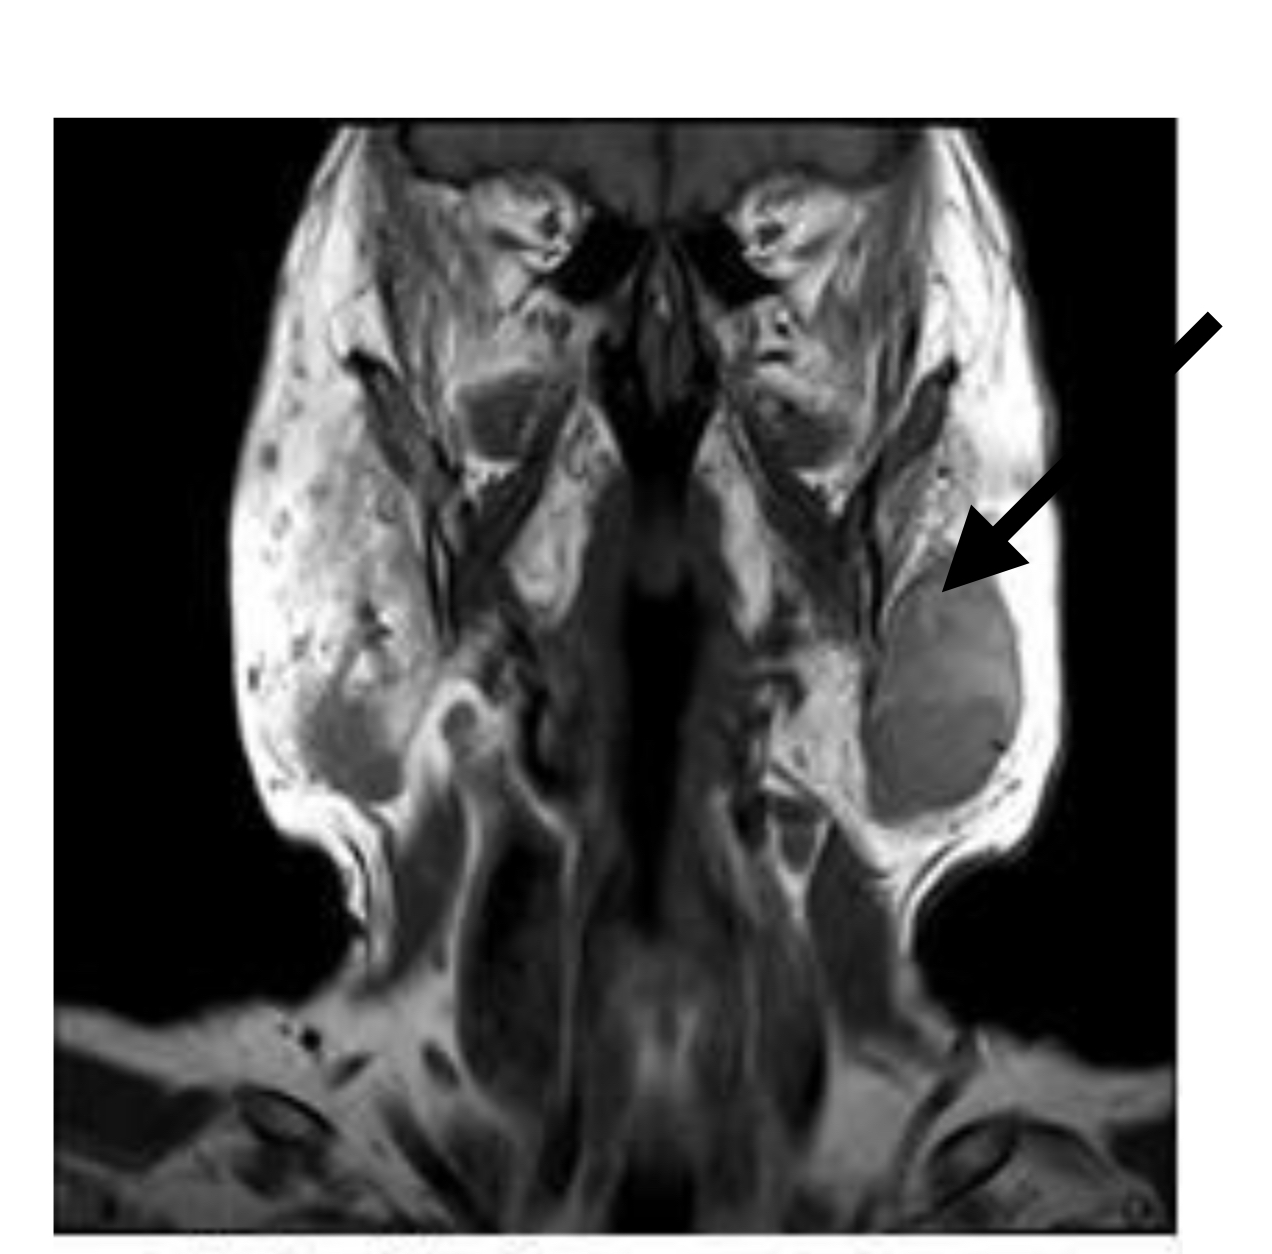

7

Q

What pathology indicated?

A

Mass - right parotid gland

8

What does arrow indicate?

left parotid mass

9

What does arrow indicate ?

submandibular gland

10

Vocal cord Schwannoma